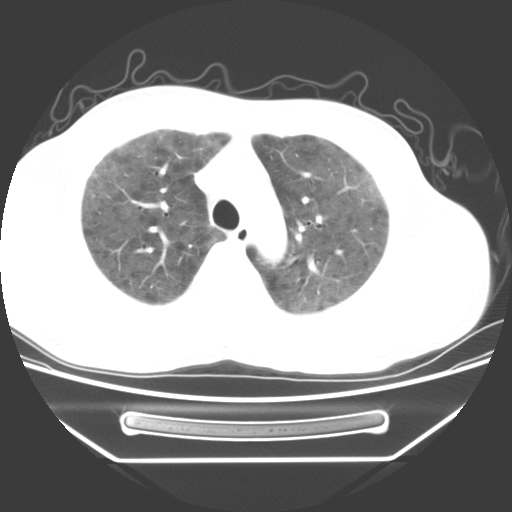

病人55岁,咳嗽,胸闷

忘了传病史了,病人55岁,咳嗽,胸闷

两肺部呈“毛玻璃”状改变,原因待查考虑感染性病变

病人是否发烧,两肺“磨玻璃”影,其间见空气支气管征和碎路石征。考虑肺泡蛋白沉着症。

两肺广泛对称磨玻璃样影,密度不均,考虑机遇性肺部感染。

双肺弥漫磨玻璃样病变,病史很重要。有感冒或发烧史,甲流不除外。无发烧可考虑肺泡蛋白沉积,但肺泡蛋白沉积边缘往往较清晰,与正常肺组织分界清晰

两肺弥漫间质性病变,考虑肺泡蛋白沉着症。建议进一步检查。